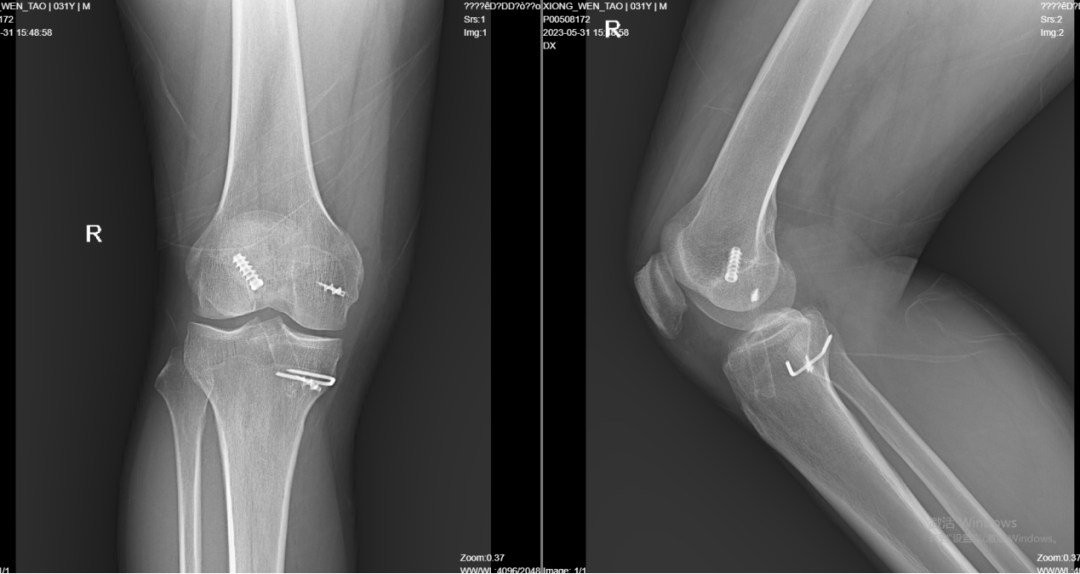

*入院当天的医学影像检查

面对医学影检查的结果,患者甚至有些不理解:虽然右膝关节周缘能见到陈旧手术疤痕,但愈合良好,为什么近期出现疼痛和异响?通过怎样的手术治疗,才能确保今后不再旧病复发?

对此,济南市中心医院东院关节外科主任高玉镭向患者解释说:此次外伤再次造成右膝前交叉韧带断裂,由于年轻、活动量大,前交叉韧带功能失效会造成膝关节不稳、退变加速,出现膝关节疼痛。需再次行膝关节前交叉韧带翻修重建术,但此次手术因为原有内置物及骨道影响,手术难度较初次手术大,术后还需规范功能锻炼,以达到手术目的。